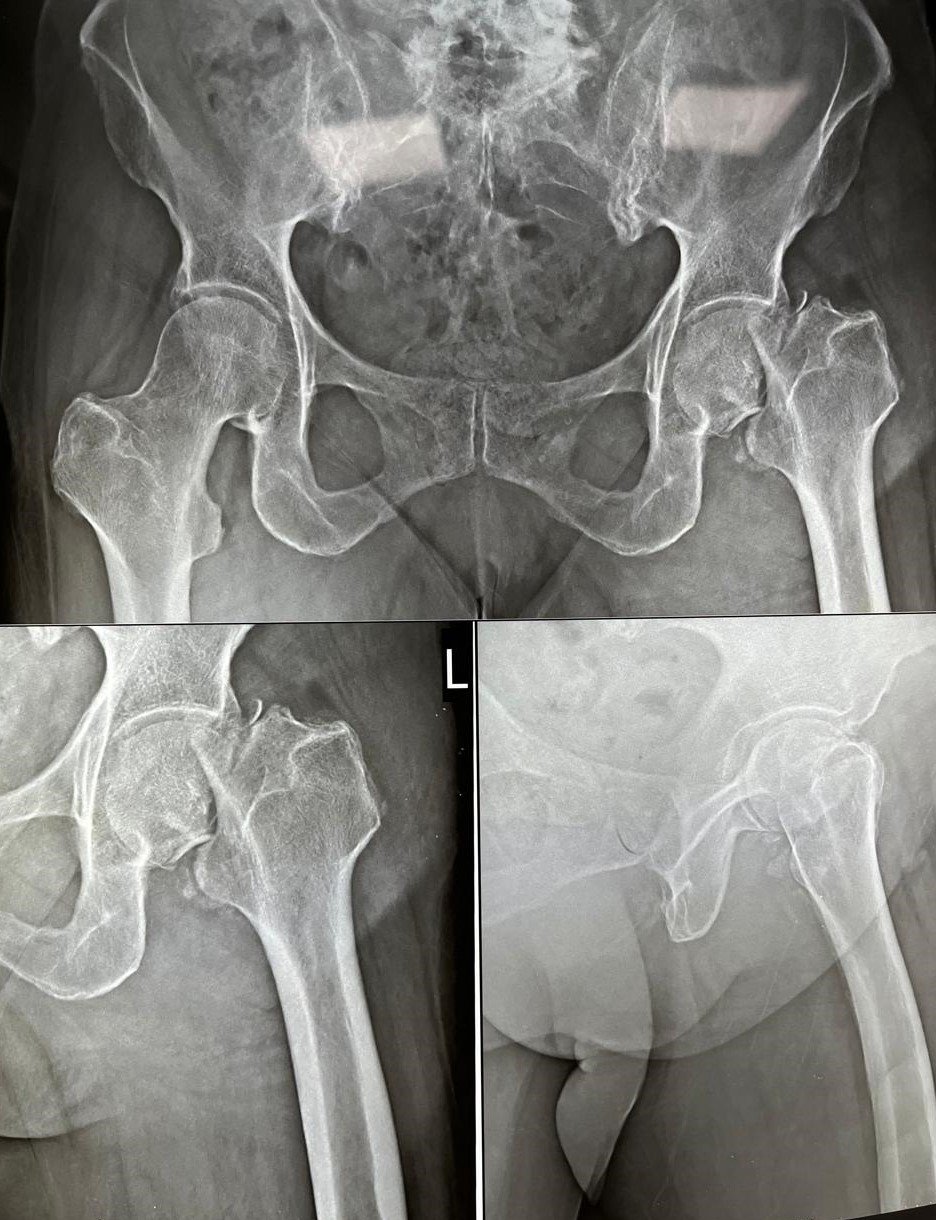

Garden Type IV Fracture Neck of Femur

Pre-Op X-Ray